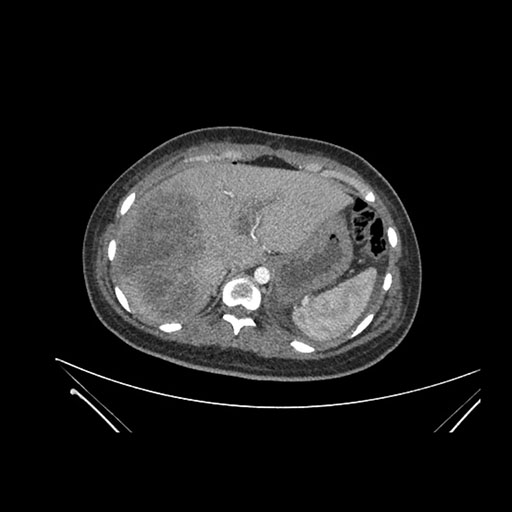

Imaging Analysis

Look through the patient's CT scan to identify any areas of concern for the necessary procedure.

Axial Venous